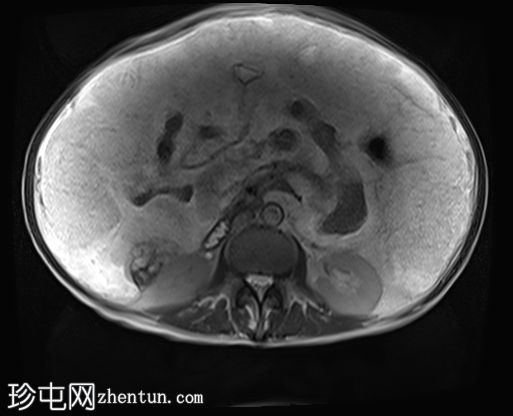

冠状位

T2

升结肠壁增厚,尤其前壁,形成肿块,T2信号高,提示其为黏液性肿块。肿块无扩散受限,增强扫描后几乎无强化。

腹腔内可见大量T2信号高、T1信号低至中等的包裹性积液,与腹膜凹陷相符,并导致内脏表面(尤其是肝脏和脾脏)呈扇贝状。这些表现是腹膜假黏液瘤的特征性表现,可能由黏液性肿瘤播散引起。